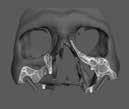

A 10 éves férfi páciens a felső frontfogai késői/nem megvalósuló előtörése miatt kereste fel a rendelőnket. A klinikai és a radiológiai vizsgálat során a jobb felső nagymetszőfog impakcióját észleltük (1. ábra). A fog horizontális tengelyállással és dilacerált gyökérrel rendelkezett. A felső dentális középvonal a fogak vándorlása miatt jelentős mértékben elcsúszott. A bal felső kismetszőfog is rendkívül kedvezőtlen pozícióba került.

Dr. Kazem Dalaie, dr. Samin Ghaffari, dr. Mazir Mir (Irán, Németország) 1. a ábra: Az intraorális felvételen jól látható a jobb felső nagymetszőfog lehetséges impakciójára utaló foghiány.

1. b ábra: A panoráma röntgenfelvételen megfigyelhető a teljes impakcióban lévő jobb felső nagymetszőfog. 1. c ábra: A CBCT felvétel is igazolja a jobb felső nagymetszőfog impakcióját.

4. a ábra: A CBCT felvétel igazolja, hogy a jobb felső nagymetszőfog megfelelő pozícióba került. Az ínyszél lefutása kedvező, a fog gyökere körül elfogadható mennyiségű csontállomány ábrázolódik, valamint a gyökérfelszívódás mértéke sem túl kifejezett.

A kezelés befejezésekor a páciens mosolya drámai mértékben javult, továbbá a frontfogak elhelyezkedése és az ínyszél lefutása is szemmel látható módon kedvezőbbé vált (4. ábra). A kezelés végén készült CBCT felvétel nem mutatta

csontfelszívódás jelenlétét, és csupán minimális mértékű gyökérfelszívódás bekövetkezését igazolta.

4. b ábra: A panoráma röntgenfelvétel is alátámasztja a CBCT felvételen látottakat. 4. c ábra: Az intraorális felvételen megfelelő fogpozíciók és kedvező ínyszéli lefutás ábrázolódik.

5. a ábra: 5. b ábra: A végső állapotról készült 5. c ábra: A végső állapotról készült